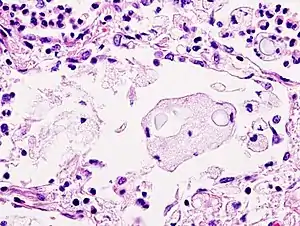

Biopsy

Mucicarmine stain: bright pink cryptococcosis capsule[33]

Field stain: thick cryptococcosis capsule

H&E stain: histiocytic penumonia_Alcian_blue-PAS.jpg.webp)